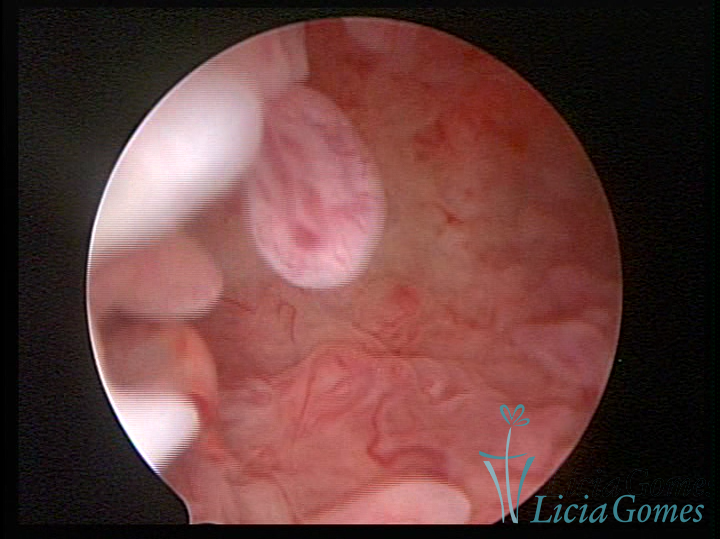

Este pode apresentar uma gama variável de aspectos macroscópicos, com aspecto pseudopolipoide; lembrando tecido cerebroide ou com reação deciduoide;a vascularização superficial é mais evidente e com vasos em formatos de saca-rolha ou espirais visualizando também a vascularização com atípias, com aumento do calibre dos vasos superficiais, pode ser encontrado também tecido em necrose, poderá haver um pequenos dendritos (papilomatoso).